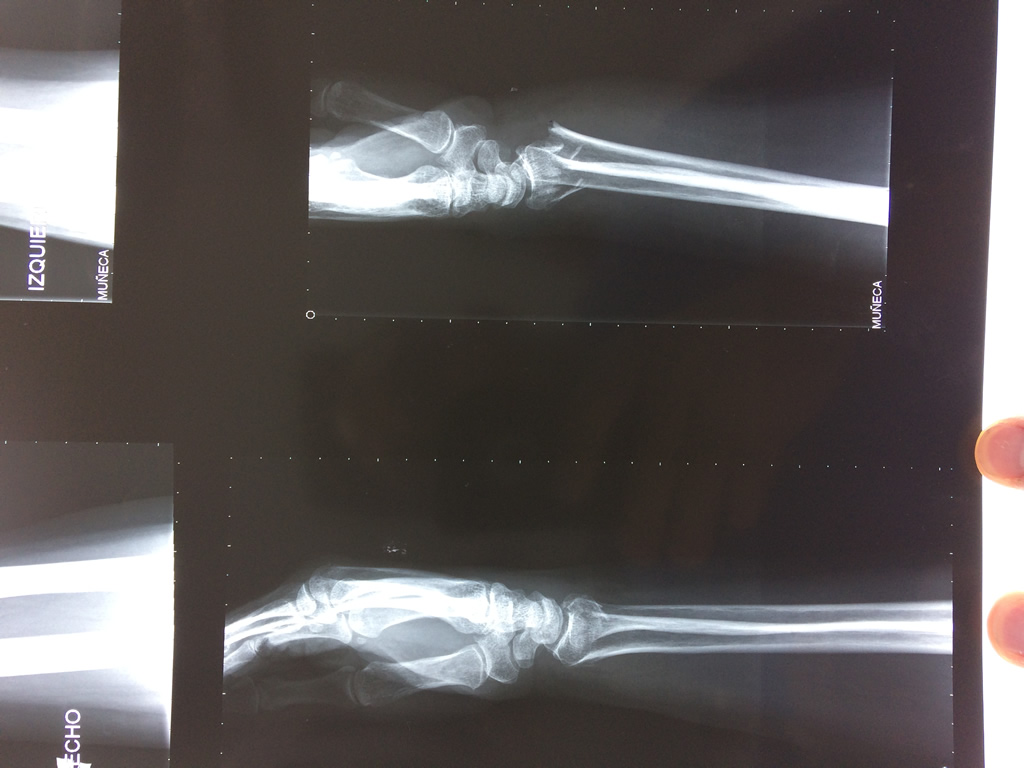

Cirugías de Muñecas

Los procedimientos más comunes en cirugía de la mano son aquellos destinados a reparar traumatismos, incluyendo lesiones de tendones, nervios, vasos sanguíneos, y articulaciones; huesos fracturados; y quemaduras, cortes, y otros daños de la piel.